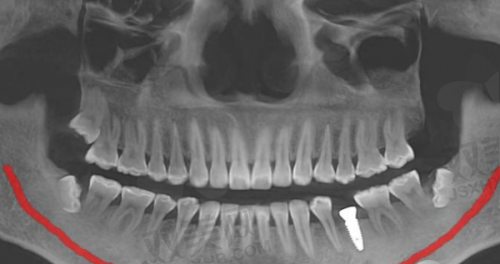

1. **精良的设备**:医院引进了国内外精良的口腔诊疗设备,如口腔 CT、数字化牙片机、激光治疗仪等。这些设备能够提供更加正确的诊断结果,为治疗方案的制定提供有力依据。例如,口腔 CT 可以清晰地显示牙齿和颌骨的内部结构,帮助医生更好地了解患者的病情,制定更加精细的治疗方案。